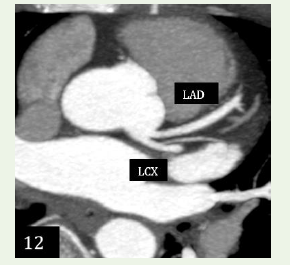

Case 5: A 48-year-old female with chest pain for 2 days, normal echocardiography, mildly positive for inducible ischemia in TMT with hypercholesterolemia demonstrated an anomalous separate origin of Left anterior descending and left circumex artery from left coronary sinus.

Figure 12: Case 5: Maximum intensity projection reconstruction & 3D

volume rendered reformation shows an anomalous separate origin of Left

anterior descending & left circumflex artery from left coronary sinus